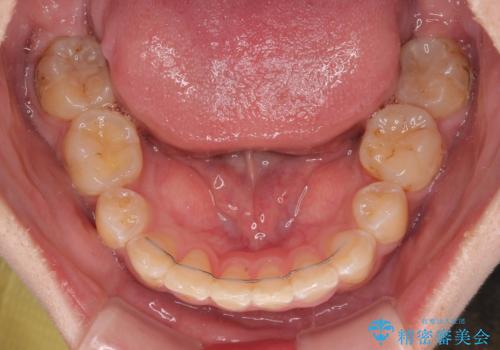

- 八重歯や埋伏している奥歯など、多くの難しい問題を抱えている患者様です。

重度叢生のため、大臼歯をしっかりと咬合させるために、下顎は左右第二小臼歯を、上顎は前歯部の叢生を解消するために左右第一小臼歯を抜歯し、口元の突出感を改善するために、上顎大臼歯が前方に移動しないようにするために、補助装置による架強固定を行うこととしました。

叢生は思ったよりも早期に改善されましたが、舌の突出癖による上下前歯の非接触が全く改善されず、2年間ほど治療期間が延びる結果となってしまいました。